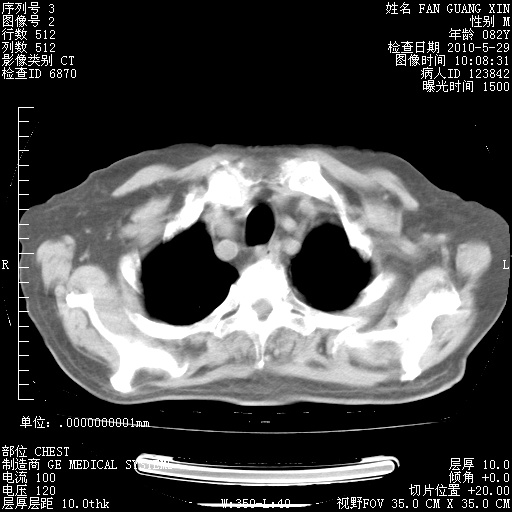

再治疗10天后的肺部CT

再治疗10天后的肺部CT 纵膈窗